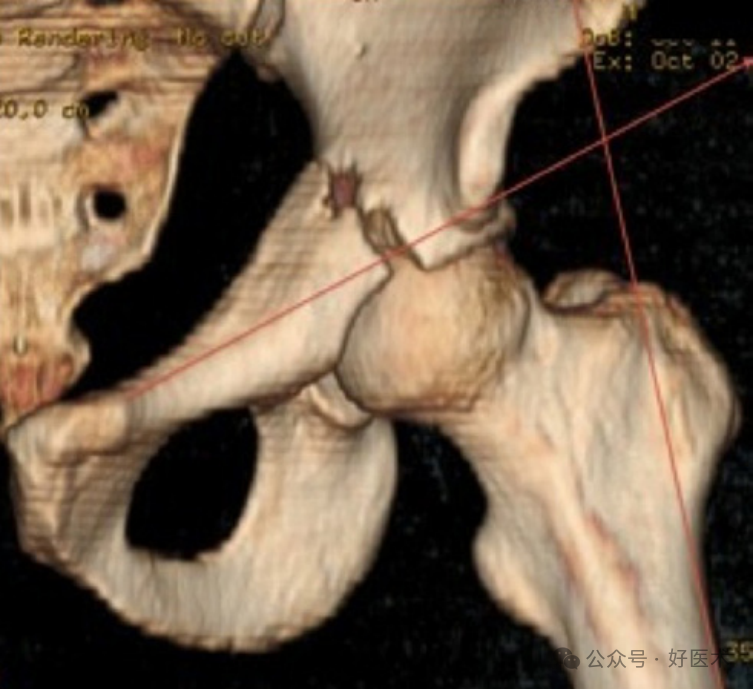

进针点

**进钉点在临床上较难找到。推荐在骨盆前后位(AP)片上,皮肤切口位于两条线的交点处:一条是通过大粗隆的股骨外侧边缘延长线,另一条是从耻骨联合到髂前下棘的连线。(下图)

顺行前柱螺钉在外髂骨的**进钉点曾被多位作者描述过。根据Letournel的说法,起始区域位于髂骨外侧,大约在髋臼最高点上方3—4厘米处,略偏臀中肌线后方的一个2厘米范围内。Ebraheim等人将进钉点描述为位于髋臼上缘上方46±6毫米处,以及连接大坐骨切迹顶端和ASIS与AIIS之间中点的线的中点上方16毫米处;矢状面角度为90.6°,横向角度为29°。Yi等人将入口点描述为“位于臀中肌柱髋臼稍上方,这是一块从髋臼延伸到髂嵴的增厚骨骼。”顺行前柱螺钉的插入点标志位于两条垂直线的交点处,一条线从髂前下棘的尖端引出,另一条线从髋臼上缘引出。根据骨性通道的大小,顺行插入在具有8.0 mm管径的患者中,**入口点的可能区域为2.5 cm²,在具有14.0 mm管径的患者中为5.7 cm²。顺行前柱螺钉的进针点与大坐骨切迹的顶点之间的距离为37–42 mm。

Eastman 描述,进入点 通常位于髋臼穹隆上部靠近臀中肌柱基部的几厘米处。Bozzio等人使用常规的前后位X光片,将ACS的起点定义为股骨干轴外侧边界与耻骨结节到AIIS下缘的交点。使用闭孔斜位和入口位,通过克氏针确认螺钉路径。